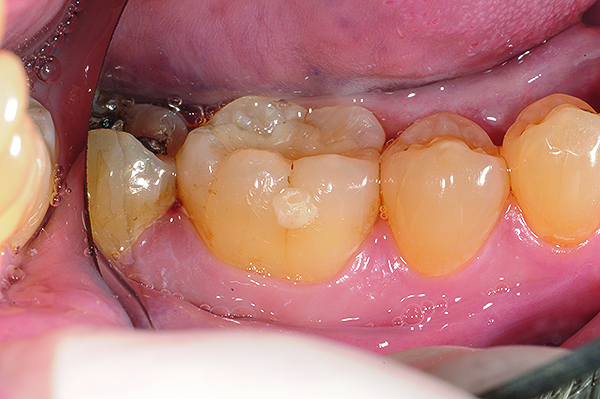

Fig 2 and Fig 3. In Case 1, occlusal (Fig 2) and buccal (Fig 3) preoperative views of defective Class I and Class V amalgam restorations on mandibular first permanent molar.

Figure 2

Figure 3